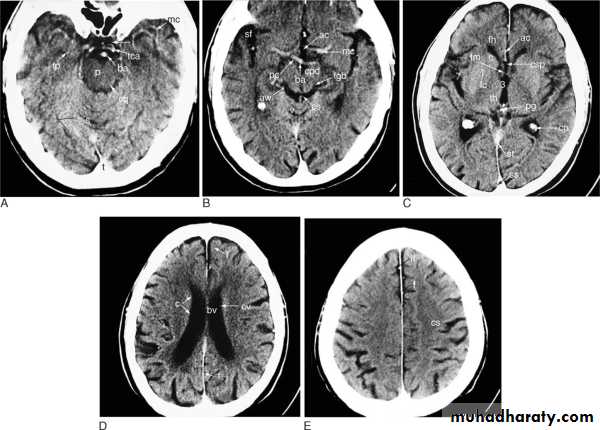

CT SCAN